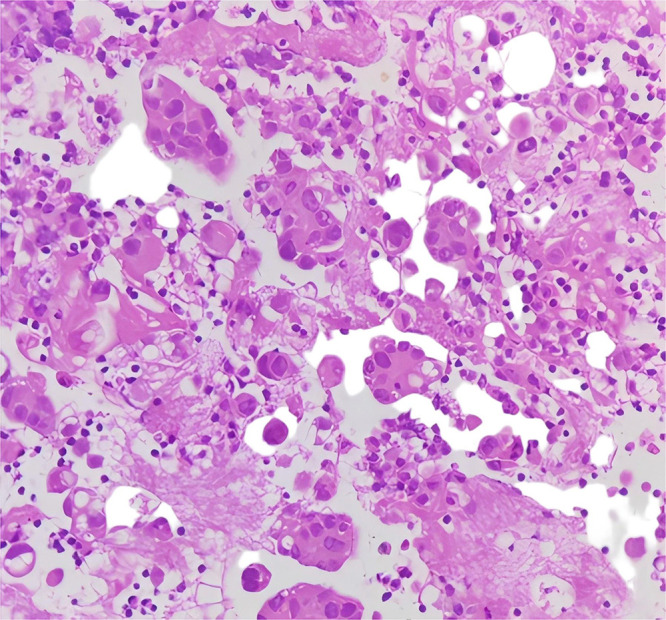

本病例报告报告了一名67岁男性,诊断为IV期肺腺癌,伴有罕见的EGFR外显子18/20突变(Gly719Cys/Ser768Ile)和并发的TP53突变,并伴有肾病综合征。针对NSCLC中罕见EGFR突变的批准EGFR- tkis的缺乏,加上肾病综合征引起的肾损害、低白蛋白血症和常规治疗难治的大量胸腔积液,促使了个性化多模式方法的发展。实施白蛋白结合紫杉醇、胸内灌注恩度(重组人内皮抑素)和中药的多模式治疗方案,实现了有效的疾病控制。值得注意的是,该治疗导致肿瘤明显缩小(RECIST 1.1的缩小率为48.1%),恶性胸腔积液完全消除,肾病综合征参数明显改善。靶向化疗、抗血管生成治疗和基于中药的症状调节的协同作用,突出了综合治疗具有复杂分子特征和多系统并发症的晚期恶性肿瘤的潜力。

This case report presents a 67-year-old male diagnosed with stage IV lung adenocarcinoma harboring rare EGFR exon 18/20 mutations (Gly719Cys/Ser768Ile) and a concurrent TP53 mutation, complicated by nephrotic syndrome. The scarcity of approved EGFR-TKIs targeting rare EGFR mutations in NSCLC, coupled with nephrotic syndrome-induced renal impairment, hypoalbuminemia, and massive pleural effusion refractory to conventional management, prompted the development of a personalized multimodal approach.A multimodal therapeutic regimen incorporating albumin-bound paclitaxel, intrathoracic perfusion of Endostar (recombinant human endostatin), and traditional Chinese medicine (TCM) was implemented, achieving effective disease control. Notably, the treatment resulted in significant tumor shrinkage (reduction rate: 48.1% by RECIST 1.1), complete resolution of malignant pleural effusion, and marked improvement in nephrotic syndrome parameters. The synergistic effects of targeted chemotherapy, anti-angiogenic therapy, and TCM-based symptom modulation highlight the potential of integrative approaches in managing advanced malignancies with complex molecular profiles and multisystem complications.